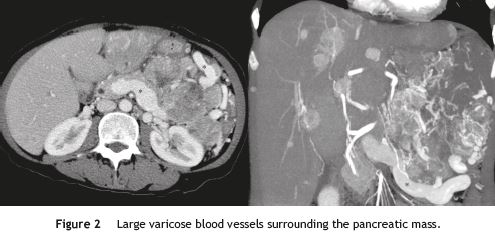

In order to clarify the nature of the abdominal mass and the etiology of the portal hypertension, the patient underwent an abdominal computed tomography (CT) scan, which revealed a large hypervascular pancreatic tumor (Fig. 1), contiguous to the left hepatic lobe, stomach and spleen, as well as multiple hepatic nodules with similar characteristics. It also showed splenic vein thrombosis and exuberant collateral blood vessels around the tumor (Fig. 2). The radiological findings were suggestive of a pancreatic neuroendocrine tumor with liver metastasis, a diagnosis subsequently confirmed by the histological and immunohistochemical studies. The investigation was completed with a chromogranin A analysis (26 nmol/L; reference upper limit 6 nmol/L) and a somatostatin-receptor scintigraphy (OctreoscanTM), which showed no additional secondary locations of the tumor.